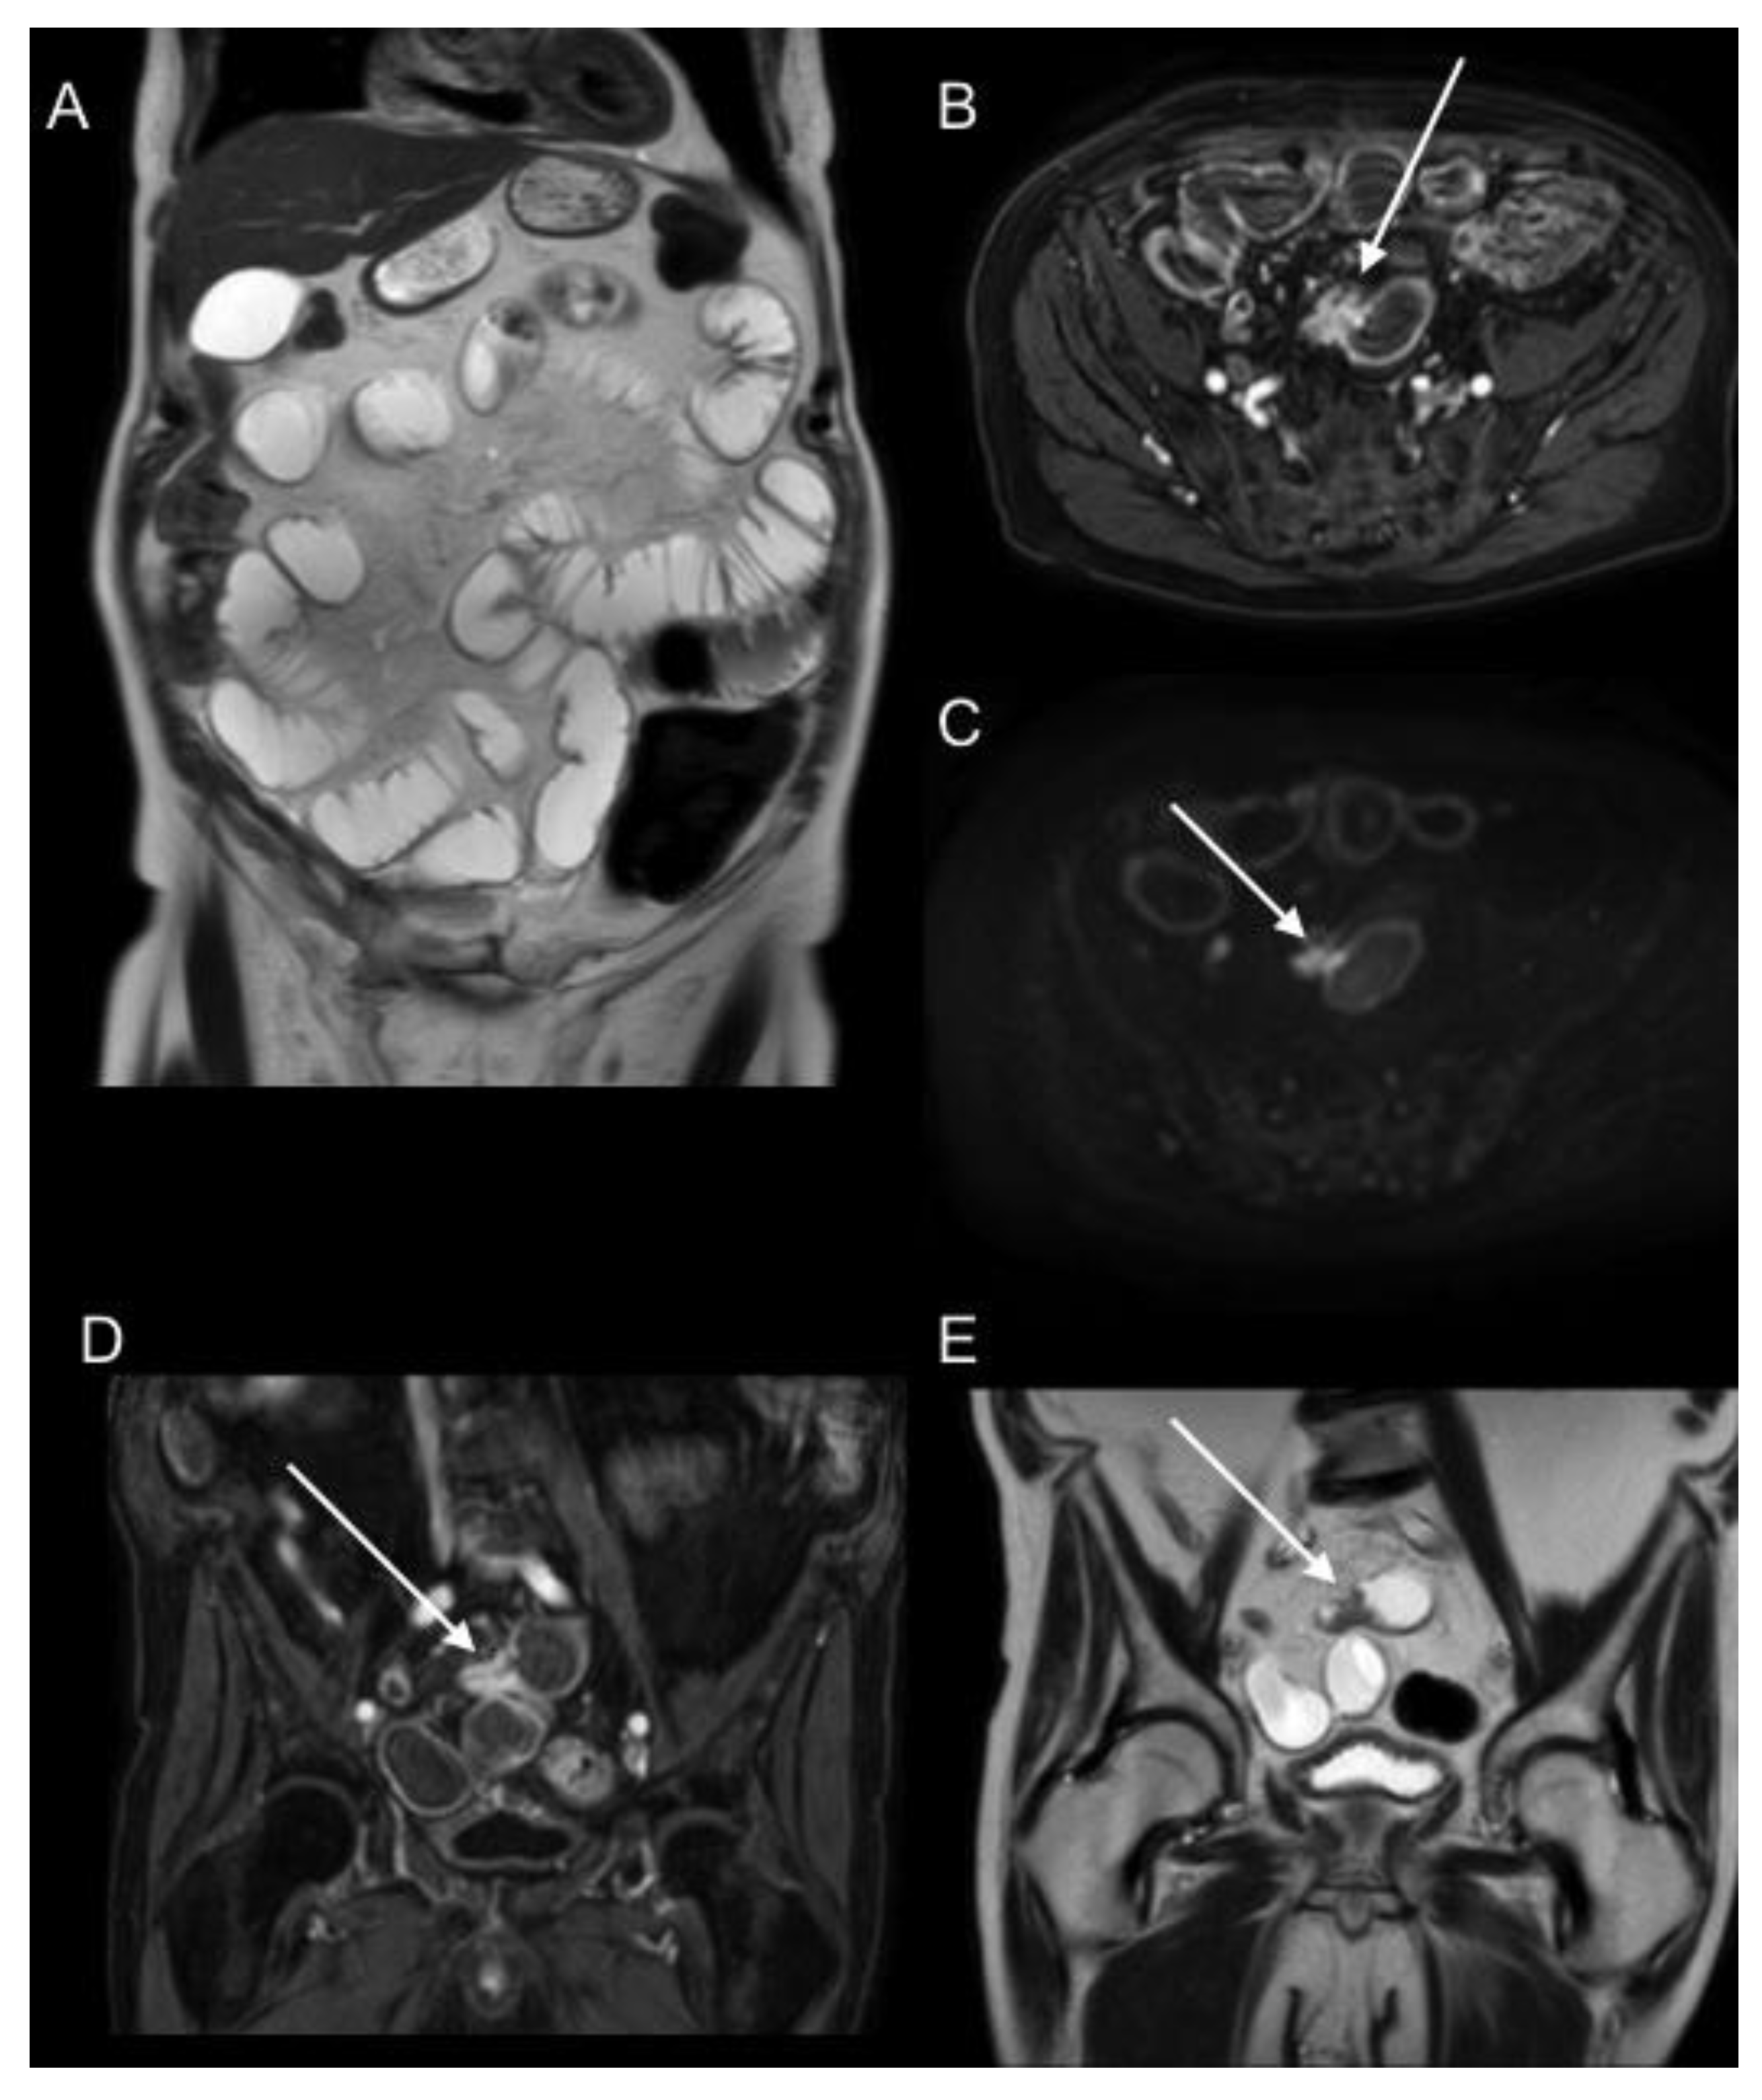

2.2. Magnetic Resonance Imaging (MRI)

- Espada, M.; Garcia-Flores, J.R.; Jimenez, M.; Alvarez-Moreno, E.; De Haro, M.; Gonzalez-Cortijo, L.; Hernandez-Cortes, G.; Martinez-Vega, V.; Sainz De La Cuesta, R. Diffusion-weighted magnetic resonance imaging evaluation of intra-abdominal sites of implants to predict likelihood of suboptimal cytoreductive surgery in patients with ovarian carcinoma. Eur. Radiol. 2013, 23, 2636–2642. [Google Scholar] [CrossRef] [PubMed]

- Fujii, S.; Matsusue, E.; Kanasaki, Y.; Kanamori, Y.; Nakanishi, J.; Sugihara, S.; Kigawa, J.; Terakawa, N.; Ogawa, T. Detection of peritoneal dissemination in gynecological malignancy: Evaluation by diffusion-weighted MR imaging. Eur. Radiol. 2007, 18, 18–23. [Google Scholar] [CrossRef] [PubMed]

- Garcia Prado, J.; González Hernando, C.; Varillas Delgado, D.; Saiz Martínez, R.; Bhosale, P.; Blazquez Sanchez, J.; Chiva, L. Diffusion-weighted magnetic resonance imaging in peritoneal carcinomatosis from suspected ovarian cancer: Diagnostic performance in correlation with surgical findings. Eur. J. Radiol. 2019, 121, 108696. [Google Scholar] [CrossRef]